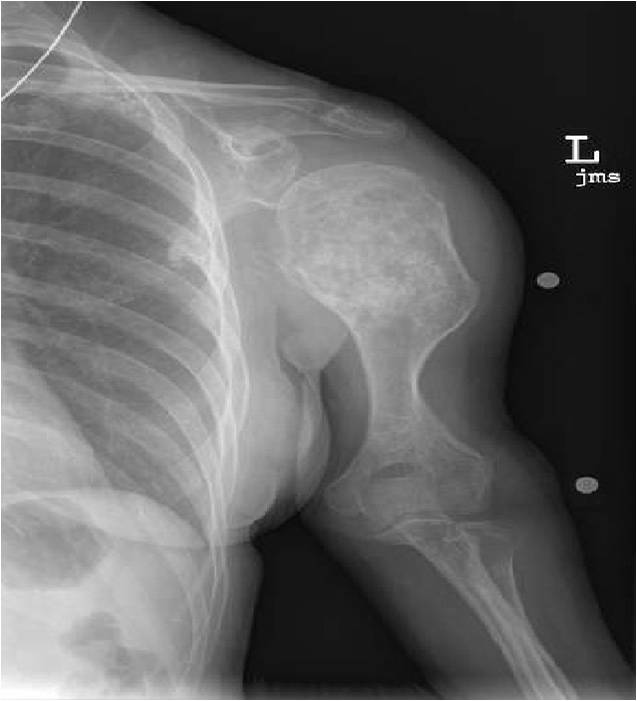

- Proximal Humerus, Femur most common long bones

- Localized, radiolucent defect usually with punctate calcifications

- Calcifications are typical but not always present

- Matrix may demonstrate various degrees of calcification

- Calcifications are stippled, punctate, popcorn like calcifications and “Ring and Arc” calcifications

- Cartilage tumors grow in a lobular manner. The perimeters of the lobules undergo

- enchondral ossification that may calcify. If the entire perimeter of the lobule calcifies it appears

- radiographically as a “Ring”. If a portion of the perimeter of a lobule calcifies it forms an “Arc” on

- an X-ray.

Plain X-Ray:

- Geographic lytic lesion

- Central often metaphyseal in long bones

- Can be eccentric also

- Expansile remodeling with thinned cortex

- Chondroid matrix with calcifications in majority of tumors

- Approximately 20% have limited or no calcifications